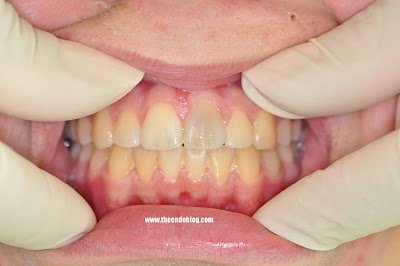

This 13 year old boy previously suffered a traumatic injury. Tooth #8 has discolored. The tooth is asymptomatic. Non-responsive to thermal testing, normal to percussion and probing.

After 1 week, pt returns and the internal bleach is removed. This tooth will be recalled to monitor vitality over time.